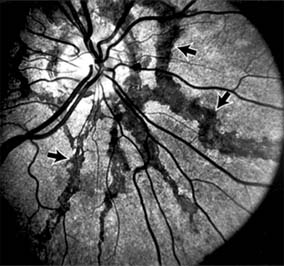

Chapter 10: Retina DISEASES OF THE MACULA AGE-RELATED MACULAR DEGENERATION Age-related macular degeneration is the leading cause of permanent blindness in the elderly. The exact cause is unknown, but the incidence increases with each decade over age 50. Other associations besides age include race (usually Caucasian), sex (slight female predominance), family history, and a history of cigarette smoking. The disease includes a broad spectrum of clinical and pathologic findings that can be classified into two groups: nonexudative ("dry") and exudative ("wet"). Although both types are progressive and usually bilateral, they differ in their manifestations, prognosis, and management. The more severe exudative form accounts for approximately 90% of all cases of legal blindness due to age-related macular degeneration. 1. NONEXUDATIVE MACULAR DEGENERATION Nonexudative age-related macular degeneration is characterized by variable degrees of atrophy and degeneration of the outer retina, retinal pigment epithelium, Bruch's membrane and choriocapillaris. Of the ophthalmoscopically visible changes in the retinal pigment epithelium and Bruch's membrane, drusen are the most typical (Figure 10-1). Drusen are discrete, round, yellow-white deposits of variable size beneath the pigment epithelium and are scattered throughout the macula and posterior pole. With time, they may enlarge, coalesce, calcify, and increase in number. Histopathologically, most drusen consist of focal collections of eosinophilic material lying between the pigment epithelium and Bruch's membrane; they therefore represent focal detachment of the pigment epithelium. In addition to drusen, clumps of pigment irregularly dispersed within depigmented areas of atrophy may progressively appear throughout the macula. The level of associated visual impairment is variable and may be minimal. Fluorescein angiography demonstrates irregular patterns of retinal pigment epithelial hyperplasia and atrophy. Electrophysiologic testing in most patients is normal. There is no generally accepted treatment or means of prevention of this type of macular degeneration. Laser retinal photocoagulation appears to have a beneficial effect on drusen but has not yet been shown to improve visual outcome. Although high plasma levels of antioxidants are associated with a reduced risk of age-related macular degeneration, the use of vitamin supplements does not appear to be preventive. Most patients with macular drusen never experience significant loss of central vision; the atrophic changes may stabilize or progress slowly. However, the exudative stage may develop suddenly at any time, and in addition to regular ophthalmic examinations, patients are given an Amsler grid ( 2. EXUDATIVE MACULAR DEGENERATION Although patients with age-related macular degeneration usually manifest nonexudative changes only, the majority of patients who experience severe vision loss from this disease do so from the development of subretinal neovascularization and related exudative maculopathy. Serous fluid from the underlying choroid can leak through small defects in Bruch's membrane, causing focal detachment of the pigment epithelium. Additional fluid may lead to further separation of the overlying sensory retina, and vision usually decreases if the fovea is involved. Retinal pigment epithelial detachments may spontaneously flatten, with variable visual results, and leave a geographic area of depigmentation at the involved site. Ingrowth of new vessels from the choroid into the subretinal space is the most important change that predisposes patients with drusen to macular detachment and irreversible loss of central vision. These new vessels grow in a flat cartwheel or sea-fan configuration away from their site of entry into the subretinal space. The clinical changes of early subretinal neovascularization are subtle and may be easily overlooked; during this occult stage of new vessel formation, the patient is asymptomatic, and the new vessels may not be apparent either ophthalmoscopically or angiographically. The ophthalmologist must maintain a high index of suspicion that subretinal neovascularization is present whenever a patient with evidence of age-related macular degeneration has sudden or recent central vision loss, including blurred vision, distortion, or a new scotoma. If the fundus examination reveals subretinal blood, exudate, or a grayish-green choroidal lesion in the macula, there is great likelihood that neovascularization is present, and a fluorescein or indocyanine green angiogram should be obtained promptly to determine if a treatable lesion can be identified. Although some subretinal neovascular membranes may spontaneously regress, the natural course of subretinal neovascularization in age-related macular degeneration is toward irreversible loss of central vision over a variable period of time. The sensory retina may be damaged by long-standing edema, detachment, or underlying hemorrhage. Furthermore, a hemorrhagic detachment of the retina may undergo fibrous metaplasia, resulting in an elevated subretinal mass called a disciform scar. This elevated fibrovascular mound of variable size represents the cicatricial end stage of exudative age-related macular degeneration. It is usually centrally located and results in permanent loss of central vision. Treatment In the absence of subretinal neovascularization, no medical or surgical treatment of serous retinal pigment epithelial detachment is of proved benefit. The use of parenteral alpha interferon, for example, has not been effective for this disease. However, if a well-defined extrafoveal ( Krypton laser photocoagulation of juxtafoveal (<200 Following successful photocoagulation of a subretinal neovascular membrane, recurrent neovascularization either contiguous with or remote from the laser scar may occur in one-half of cases by 2 years. Recurrence is often accompanied by severe vision loss, so that careful monitoring with Amsler grids, ophthalmoscopy, and angiography is essential. Low-dose radiotherapy has provided encouraging results in patients with subfoveal neovascularization. Patients with impaired central vision in both eyes may benefit from a variety of low vision aids. CENTRAL SEROUS CHORIORETINOPATHY Central serous chorioretinopathy is characterized by serous detachment of the sensory retina as a consequence of focal leakage of fluid from the choriocapillaris through a defect in the retinal pigment epithelium (Figures 10-2 and 10-3). This disease typically affects young to middle-aged men and may be related to life stress events. Most patients present with the sudden onset of blurred vision, micropsia, metamorphopsia, and central scotoma. Visual acuity is often only moderately decreased and may be improved to near-normal with a small hyperopic correction. The diagnosis is made by slitlamp examination of the fundus; the presence of serous detachment of the sensory retina in the absence of ocular inflammation, subretinal neovascularization, an optic pit, or a choroidal tumor is diagnostic. The retinal pigment epithelial lesion appears as a small, round or oval, yellowish-gray spot that is variable in size and may be difficult to detect without the aid of fluorescein angiography. Fluorescein dye leaking from the choriocapillaris may accumulate below the pigment epithelium or sensory retina, resulting in a variety of patterns including the well-recognized smokestack configuration. Approximately 80% of eyes with central serous chorioretinopathy undergo spontaneous resorption of subretinal fluid and recovery of normal visual acuity within 6 months after the onset of symptoms. Despite normal acuity, however, many patients have a mild permanent visual defect, such as a decrease in color sensitivity, micropsia, or relative scotoma. Twenty to 30 percent of patients will have one or more recurrences of the disease, and complications-including subretinal neovascularization and chronic cystoid macular edema-have been described in patients with frequent and prolonged serous detachments. The cause of central serous chorioretinopathy is unknown; there is no convincing evidence that the disease is either infectious or due to retinal pigment epithelial dystrophy. Argon laser photocoagulation directed to the active leak significantly shortens the duration of the sensory detachment and hastens the recovery of central vision, but there is no evidence that prompt photocoagulation reduces the chance of permanent loss of visual function. Although the complications of retinal laser photocoagulation are few, it is probably not advisable to recommend immediate photocoagulation treatment in all patients with central serous chorioretinopathy. The duration and location of disease, the condition of the fellow eye, and occupational visual requirements are all considerations upon which treatment decisions are based. MACULAR EDEMA Retinal edema involving the macula may be associated with a variety of intraocular inflammatory diseases, retinal vascular diseases, intraocular surgery, inherited or acquired retinal degenerations, medications, macular membranes, or unknown causes. Macular edema may be diffuse, with nonlocalized intraretinal fluid causing thickening of the macula. When edema fluid accumulates in honeycomb-like spaces of the outer plexiform and inner nuclear layers, it is called cystoid macular edema. On fluorescein angiography, fluorescein dye leaks from the perifoveal retinal capillaries and accumulates in a flower-petal pattern about the fovea (Figure 10-4). The most widely recognized association with cystoid macular edema is intraocular surgery. Approximately 50% of eyes undergoing uneventful intracapsular cataract extraction and 20% of eyes undergoing extracapsular cataract extraction develop angiographic cystoid macular edema. Clinically significant edema usually occurs within 4-12 weeks postoperatively, but in some instances its onset may be delayed for months or years. Many patients with cystoid macular edema of less than 6 months' duration have self-limited leakage that will resolve without treatment. Topical or local (or both) anti-inflammatory therapy may be of value in restoring visual acuity in some patients with chronic postoperative macular edema. YAG laser vitreolysis (see Chapter 24) and surgical vitrectomy may be of benefit when the macular edema is associated with vitreous tissue incarcerated in the cataract wound or adherent to anterior segment structures. When an intraocular lens implant is the cause of postoperative macular edema due to its design, positioning, or inadequate fixation, removal of the lens implant can be considered. INFLAMMATORY DISORDERS INVOLVING THE MACULA Presumed Ocular Histoplasmosis Syndrome (Figures 10-5, 10-6 and 10-7) In this disease, serous and hemorrhagic detachments of the macula are associated with multiple peripheral atrophic chorioretinal scars and peripapillary chorioretinal scarring (see Chapter 7). The syndrome usually occurs in healthy patients between the third and sixth decades of life, and the scars are probably caused by an antecedent subclinical systemic infection with Histoplasma capsulatum. The macular detachments are due to subretinal neovascularization, and the visual prognosis depends on the proximity of the neovascular membrane to the center of the fovea. If the membrane extends inside the foveal avascular zone, only 15% of eyes will retain 20/40 vision. A macular scar may change over time, and 10% of patients with normal maculae will develop new atrophic scars in this region. The relative risk of developing macular subretinal neovascularization in the second eye of an affected patient is significant, and these patients should be instructed in the frequent use of the Amsler grid and the importance of prompt examination when changes are detected. Argon laser photocoagulation of a subretinal neovascular membrane outside the foveal avascular zone in symptomatic patients is of value in preventing severe vision loss. The surgical removal of submacular membranes may prove useful in preserving vision. Acute Multifocal Posterior Placoid Pigment Epitheliopathy (AMPPPE) AMPPPE typically affects healthy young patients who develop rapidly progressive bilateral vision loss in association with ophthalmoscopically visible multifocal flat gray-white subretinal lesions involving the pigment epithelium (Figure 10-8). The cause of this disease, which in many instances is associated with evidence of an influenza-like illness, is unknown; the course and nature of the illness suggests the possibility of viral infection. The characteristic feature of the disease is the rapid resolution of the fundus lesions and a delayed return of visual acuity to near-normal levels. Although the prognosis for visual recovery in this acute self-limited disease is good, many patients will identify small residual paracentral scotomas when carefully tested. Extensive pigmentary changes remaining during the late stages of AMPPPE may mimic widespread retinal degeneration; the clinical history and normal electrophysiologic findings aid in this differential diagnosis. Geographic Helicoid Peripapillary Choroidopathy This is a chronic progressive and recurrent multifocal inflammatory disease of the retinal pigment epithelium, choriocapillaris, and choroid. It characteristically involves the juxtapapillary retina and extends radially to involve the macula and peripheral retina. The active stage manifests itself as sharply demarcated gray-yellow lesions with irregular borders that appear to involve the pigment epithelium and choriocapillaris. Vitritis, anterior uveitis, and subretinal neovascularization have been associated with this disorder. Involvement is usually bilateral, and the cause is unknown. The natural history of this indolent inflammatory disease is variable and may correlate with the presence of disease in the fellow eye. Local or systemic corticosteroid treatment may be of benefit when active inflammation is present; laser photocoagulation is administered as indicated for the complication of subretinal neovascularization. Vitiliginous Chorioretinitis (Birdshot Retinochoroidopathy) This is a syndrome characterized by diffuse cream-colored patches at the level of the pigment epithelium and choroid, retinal vasculitis associated with cystoid macular edema, and vitritis. The associations with HLA-A29 and with retinal S-antigen suggest that this disease has a genetic predisposition and that retinal autoimmunity plays a role in its manifestations. In many cases, electroretinography, electro-oculography, and dark adaptation studies are abnormal. The course of the disease is that of exacerbation and remission with variable visual outcomes; visual loss has been attributed to chronic cystoid macular edema, optic atrophy, macular scarring, or subretinal neovascularization. Corticosteroid therapy has not proved effective against this disease. Acute Macular Neuroretinopathy Acute macular neuroretinopathy is characterized by the acute onset of paracentral scotomas and mild visual acuity loss accompanied by wedge-shaped parafoveal retinal lesions in the deep sensory retina of one or both eyes. The macular lesions are subtle, reddish-brown, and best seen with a red-free light. The patients are usually young adults with a history of acute viral illness. While the retinal lesions may fade, the scotomas tend to persist and remain symptomatic. Multiple Evanescent White Dot Syndrome This is an acute and self-limited unilateral disease that affects mainly young women and is characterized clinically by multiple white dots at the level of the pigment epithelium, vitreal cells, and transient electroretinographic abnormalities. The cause is unknown. There is no evidence of associated systemic disease. The retinal lesions gradually regress in a matter of weeks, leaving only minor retinal pigment epithelial defects. ANGIOID STREAKS Angioid streaks appear as irregular, jagged tapering lines that radiate from the peripapillary retina into the macula and peripheral fundus (Figure 10-9). The streaks represent linear crack-like dehiscences in Bruch's membrane. The lesions are rarely noted in children and probably develop in the second or third decade of life. Early in the disease the streaks are sharply outlined and red-orange or brown. Subsequent fibrovascular tissue growth may partially or totally obscure the streak margins. Nearly 50% of patients with angioid streaks have an associated systemic disease. Pseudoxanthoma elasticum, Paget's disease of bone, Ehlers-Danlos syndrome, and several hemoglobinopathies and hemolytic disorders have been associated with this retinal disease, but the most common association is with age-related degeneration of Bruch's membrane. Patients with angioid streaks should be warned of the potential risk of choroidal rupture from even relatively mild eye trauma. Older patients with the disease are at risk of developing serous and hemorrhagic detachments of the retina as a consequence of subretinal neovascularization. Laser treatment may be used to photocoagulate extrafoveal neovascular membranes; however, other neovascular membranes are likely to occur. Prophylactic treatment of angioid streaks before subretinal neovascularization develops is not recommended. MYOPIC MACULAR DEGENERATION Pathologic myopia is one of the leading causes of blindness in the United States and is characterized by progressive elongation of the eye with subsequent thinning and atrophy of the choroid and pigment epithelium in the macula. Peripapillary chorioretinal atrophy and linear breaks in Bruch's membrane ("lacquer cracks") are characteristic findings on ophthalmoscopy (Figure 10-10). The degenerative changes of the macular pigment epithelium resemble those found in the older patient with age-related macular degeneration. A characteristic lesion of this disease is a raised, circular, pigmented macular lesion called a Fuchs spot. Most patients are in the fifth decade when the degenerative macular changes cause a slowly progressive loss of vision; rapid loss of visual acuity is usually caused by serous and hemorrhagic macular degeneration overlying a subretinal neovascular membrane. Fluorescein angiography in patients with pathologic myopia may show delayed filling of choroidal and retinal blood vessels. Angiography is helpful in identifying and locating the site of subretinal neovascularization in patients who develop serous or hemorrhagic detachments of the macula. Because of the frequent close proximity of the subretinal neovascular membrane to the foveola in these patients, laser photocoagulation may not be possible. As subretinal neovascular membranes tend to remain small and because photocoagulation-associated chorioretinal atrophy tends to progress in patients with pathologic myopia, retinal laser treatment is not as beneficial as in other diseases associated with macular subretinal neovascularization. The chorioretinal changes of pathologic myopia predispose the retina to breaks and thus to retinal detachment. Peripheral retinal findings may include paving stone degeneration, pigmentary degeneration, and lattice degeneration. Retinal breaks usually occur in areas involved with chorioretinal lesions, but they also arise in areas of apparently normal retina. Some of these breaks, particularly those of the "horseshoe" and round retinal tear type, will progress to rhegmatogenous retinal detachment. MACULAR HOLE A macular hole is a partial or full-thickness absence of the sensory retina in the macula. This disorder occurs most often in elderly women and is associated with elevated plasma fibrinogen levels. The typical finding on biomicroscopy of the symptomatic eye is a full-thickness, round or oval, sharply defined hole measuring one-third disk diameter in the center of the macula, which may be surrounded by a ring detachment of the sensory retina (Figure 10-11). With a full-thickness macular hole, visual acuity is impaired and metamorphopsia, as well as a central scotoma, are present on the Amsler grid. An operculum of retinal tissue may overlie the macular hole. Tangential traction from epiretinal vitreous cortex plays an important role in the pathogenesis of macular hole. Early stages of macular hole formation, such as a deep foveal yellow spot or ring, may be reversible as the posterior vitreous cortex spontaneously separates from the retina. Therapy for macular hole disease involves reattaching and potentially restoring function to the retina overlying the cuff of subretinal fluid surrounding the hole. While the anatomic results of vitrectomy surgery to close macular holes are encouraging, the clinical benefits are still under study. EPIRETINAL MACULAR MEMBRANES Fibrocellular membranes may proliferate on the surface of the retina, either in the macula or peripheral retina. Contraction or shrinkage of these epiretinal membranes may cause varying degrees of visual distortion, intraretinal edema, and degeneration of the underlying retina. Biomicroscopy usually shows retinal wrinkles and vessel tortuosity and may rarely also show retinal hemorrhages, cotton-wool spots, serous retinal detachment, and macular hole; a posterior vitreous detachment is nearly always present (Figure 10-12). Disorders associated with epiretinal membranes include retinal tears with or without rhegmatogenous retinal detachment, vitreous inflammatory diseases, trauma, and a variety of retinal vascular diseases. Patients with macular distortion and vision loss caused by epiretinal membrane contraction are usually left with stable visual acuity, suggesting that membrane contraction is a short-lived and self-limited process. Surgical peeling of severe epiretinal membranes can be performed successfully, but regrowth of epiretinal tissues occurs in some cases. There is no role for photocoagulation in the treatment of epiretinal macular membrane disease. TRAUMATIC MACULOPATHY Blunt trauma to the anterior segment of the eye may cause a contrecoup injury to the retina called commotio retinae. The retina develops a gray-white color that affects primarily the outer retina and may be confined to the macular area (Berlin's edema) or may involve extensive areas of the peripheral retina. The retinal whitening in the macular area may clear completely, or impairment of central vision may be permanent and associated with a pigmented retinal scar (Figure 10-13) or a macular hole. Trauma similar to that which causes Berlin's edema may also cause choroidal rupture with subretinal hemorrhage and permanent central vision loss. In addition to blunt trauma, several other traumatic injuries involving the macula are of importance. Purtscher's retinopathy is characterized by multiple patches of superficial retinal whitening and retinal hemorrhages in each eye of a patient after severe compression injury to the head or trunk. Terson's syndrome is seen in approximately 20% of patients after traumatic (or spontaneous) subarachnoid or subdural hemorrhage and is characterized by vitreous and superficial macular hemorrhage. Solar retinopathy refers to a specific foveolar lesion that occurs after sun-gazing and is best described as a usually bilateral sharply circumscribed and often irregularly shaped partial-thickness hole or depression in the center of the fovea. MACULAR DYSTROPHIES Macular dystrophies differ from degenerations in that the former are inherited, though not necessarily evident at birth, and are not associated with systemic diseases. Most often the disorder is restricted to the macula; it may be symmetric or asymmetric, but eventually both eyes are affected. In the early stages of some of these disorders the visual acuity may be reduced while the macular changes are subtle or absent on ophthalmoscopy, and the patient's complaint may be dismissed as spurious. Conversely, in other macular dystrophies, the ophthalmoscopic changes may be very striking at a time when the patient is free of visual symptoms. One method of classifying the more common macular dystrophies is to consider the presumptive anatomic layer or layers of the retina involved (Table 10-1). X-Linked Juvenile Retinoschisis This is a congenital disease of males characterized by a macular lesion called "foveal schisis." On slitlamp examination, foveal schisis appears as small superficial retinal cysts arranged in a stellate pattern accompanied by radial striae centered in the foveal area (Figure 10-14). Visual acuity is usually between 20/40 and 20/200; peripheral visual field abnormalities are present in the 50% of patients with associated peripheral retinoschisis. The posterior pole appears normal on fluorescein angiography, and this may be helpful in the clinical differentiation from cystoid macular edema. B wave abnormalities on the electroretinogram are consistent with the histopathologic finding of intraretinal splitting in the nerve fiber layer. Cone-Rod Dystrophies The cone-rod dystrophies constitute a relatively rare group of disorders that may be regarded as a single entity showing variable expressivity. Most cases are sporadic, but familial cases are usually transmitted by an autosomal dominant inheritance pattern. Cone-rod dystrophy is characterized by predominant involvement of the cone photoreceptors with progressive color vision defects and associated loss of visual acuity. A bilateral and symmetric bulls-eye pattern of depigmentation and a corresponding zone of hyperfluorescence surrounding a central nonfluorescent spot (similar to that seen in chloroquine retinopathy) are the most commonly described biomicroscopic and angiographic changes in these patients (Figure 10-15). As the disease progresses, the electroretinogram shows marked loss of cone function associated with a slight to moderate loss of rod function. Histopathologic study shows absence of macular and paramacular photoreceptors, and there is associated pigment epithelium degeneration. Fundus Albipunctatus Fundus albipunctatus is an autosomal recessive nonprogressive dystrophy characterized by a myriad of discrete small white dots at the level of the pigment epithelium sprinkled about the posterior pole and midperiphery of the retina. Patients are night-blind with normal visual acuity, normal visual fields, and normal color vision. While the electroretinogram and electro-oculogram are usually normal, dark adaptation thresholds are markedly elevated. Retinitis punctata albescens is the less common progressive variant of this dystrophy. Fundus Flavimaculatus (Stargardt's Disease) This is a bilateral and symmetric autosomal recessive disorder characterized by multiple yellow-white fleck lesions of variable size and shape confined to the retinal pigment epithelium (Figure 10-16). Many patients suffer central visual loss in childhood; however, macular involvement and the ultimate visual outcome are variable. Fluorescein angiography is important in differentiating flecks from drusen; the former are usually hypofluorescent. The electroretinogram and electro-oculogram are usually normal. Histopathologic abnormalities are confined to the pigment epithelium; the yellow flecks seen clinically are dense accumulations of lipofuscin within engorged pigment epithelial cells. Vitelliform Dystrophy (Best's Disease) Vitelliform dystrophy is an autosomal dominant disorder with variable penetrance and expressivity with onset usually in childhood. The ophthalmoscopic appearance is variable and ranges from a mild pigmentary disturbance within the fovea to the typical vitelliform or "egg yoke" lesion located within the central macula (Figure 10-17). This characteristic cyst-like lesion is generally quite round and well demarcated and contains homogeneous opaque yellow material lying at the apparent level of the retinal pigment epithelium. The "egg yoke" may degenerate and be associated with subretinal neovascularization, subretinal hemorrhage, and extensive macular scarring. Visual acuity often remains good, and the electroretinogram is normal; the distinctly abnormal electro-oculogram is the hallmark of this disease. PREVIOUS | NEXT Page: 1 | 2 | 3 | 4 | 5 | 6 | 7 | 8 | 9 10.1036/1535-8860.ch10 |